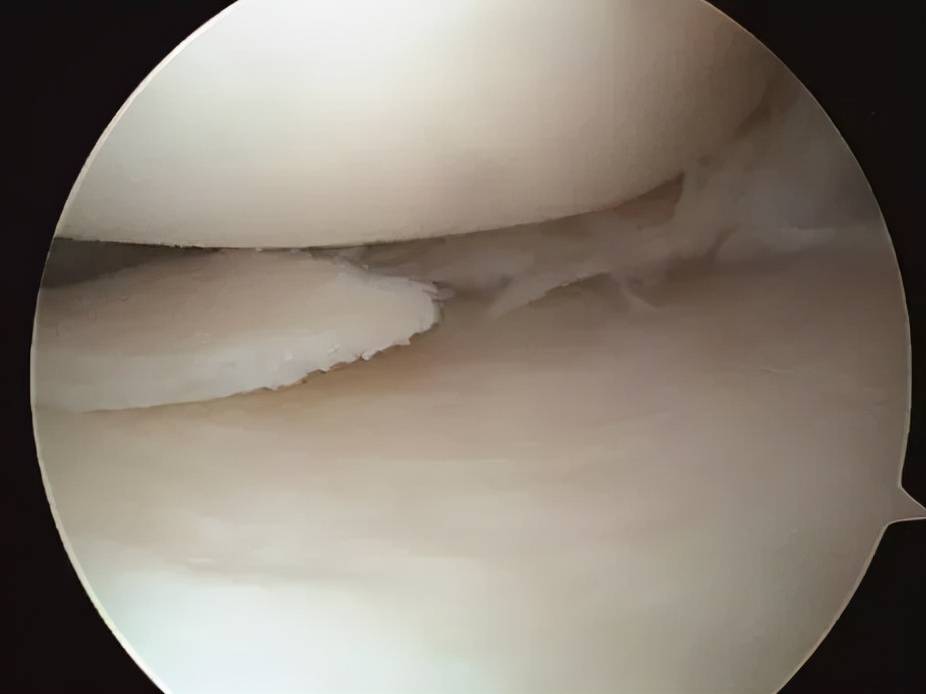

当进入到关节腔并清理周围增生的滑膜组织后,可以清晰地见到破损的半月板,半月板的损伤类型有多种( 不一定要“换膝盖”!关节镜微创手术,小切口,解决膝骨性关节炎! ),但处理原则是①去除不稳定的撕裂瓣;②切除缘修整成圆弧状;③尽可能保留半月板环的完整和宽度,对于保留功能具有重要意义;④防止损伤周围软骨。